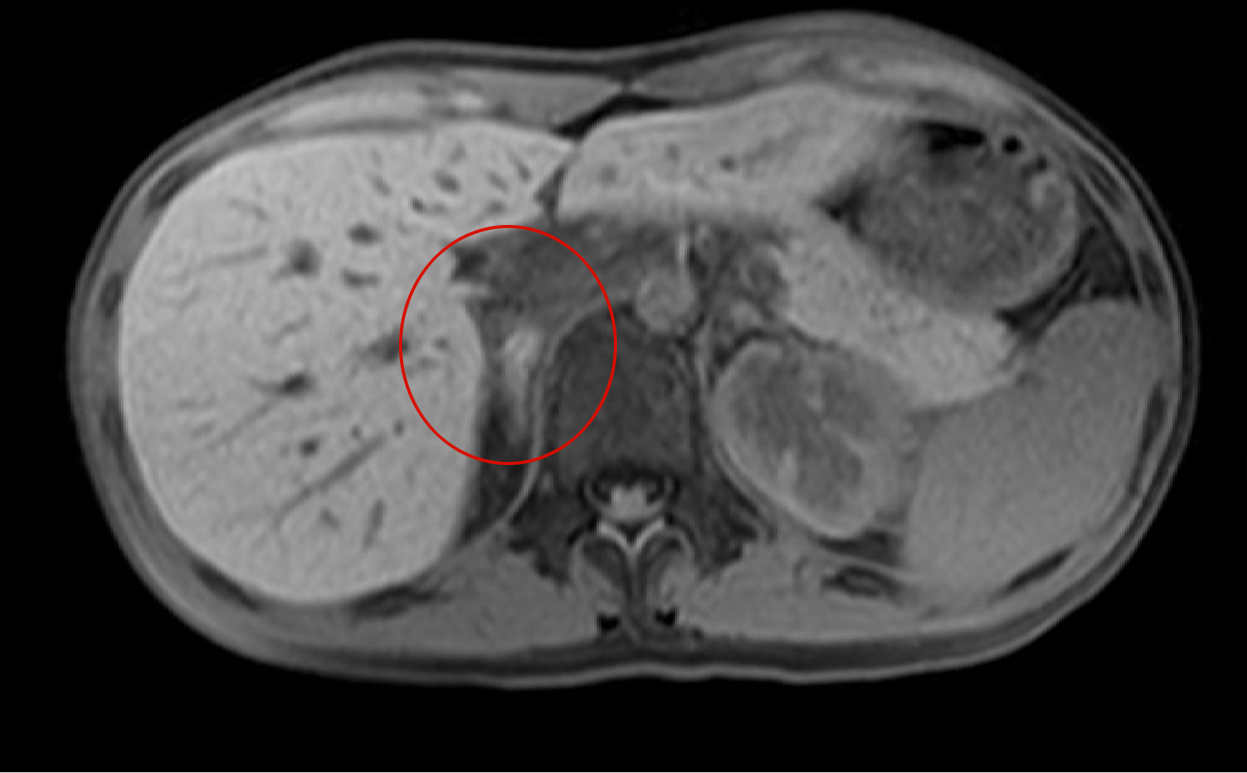

- 【3週間後 MRI 脂肪抑制T1WI】

-

- 右副腎脂肪抑制T1WIで高信号となっており副腎出血を疑う。

- 左副腎の腫大は改善